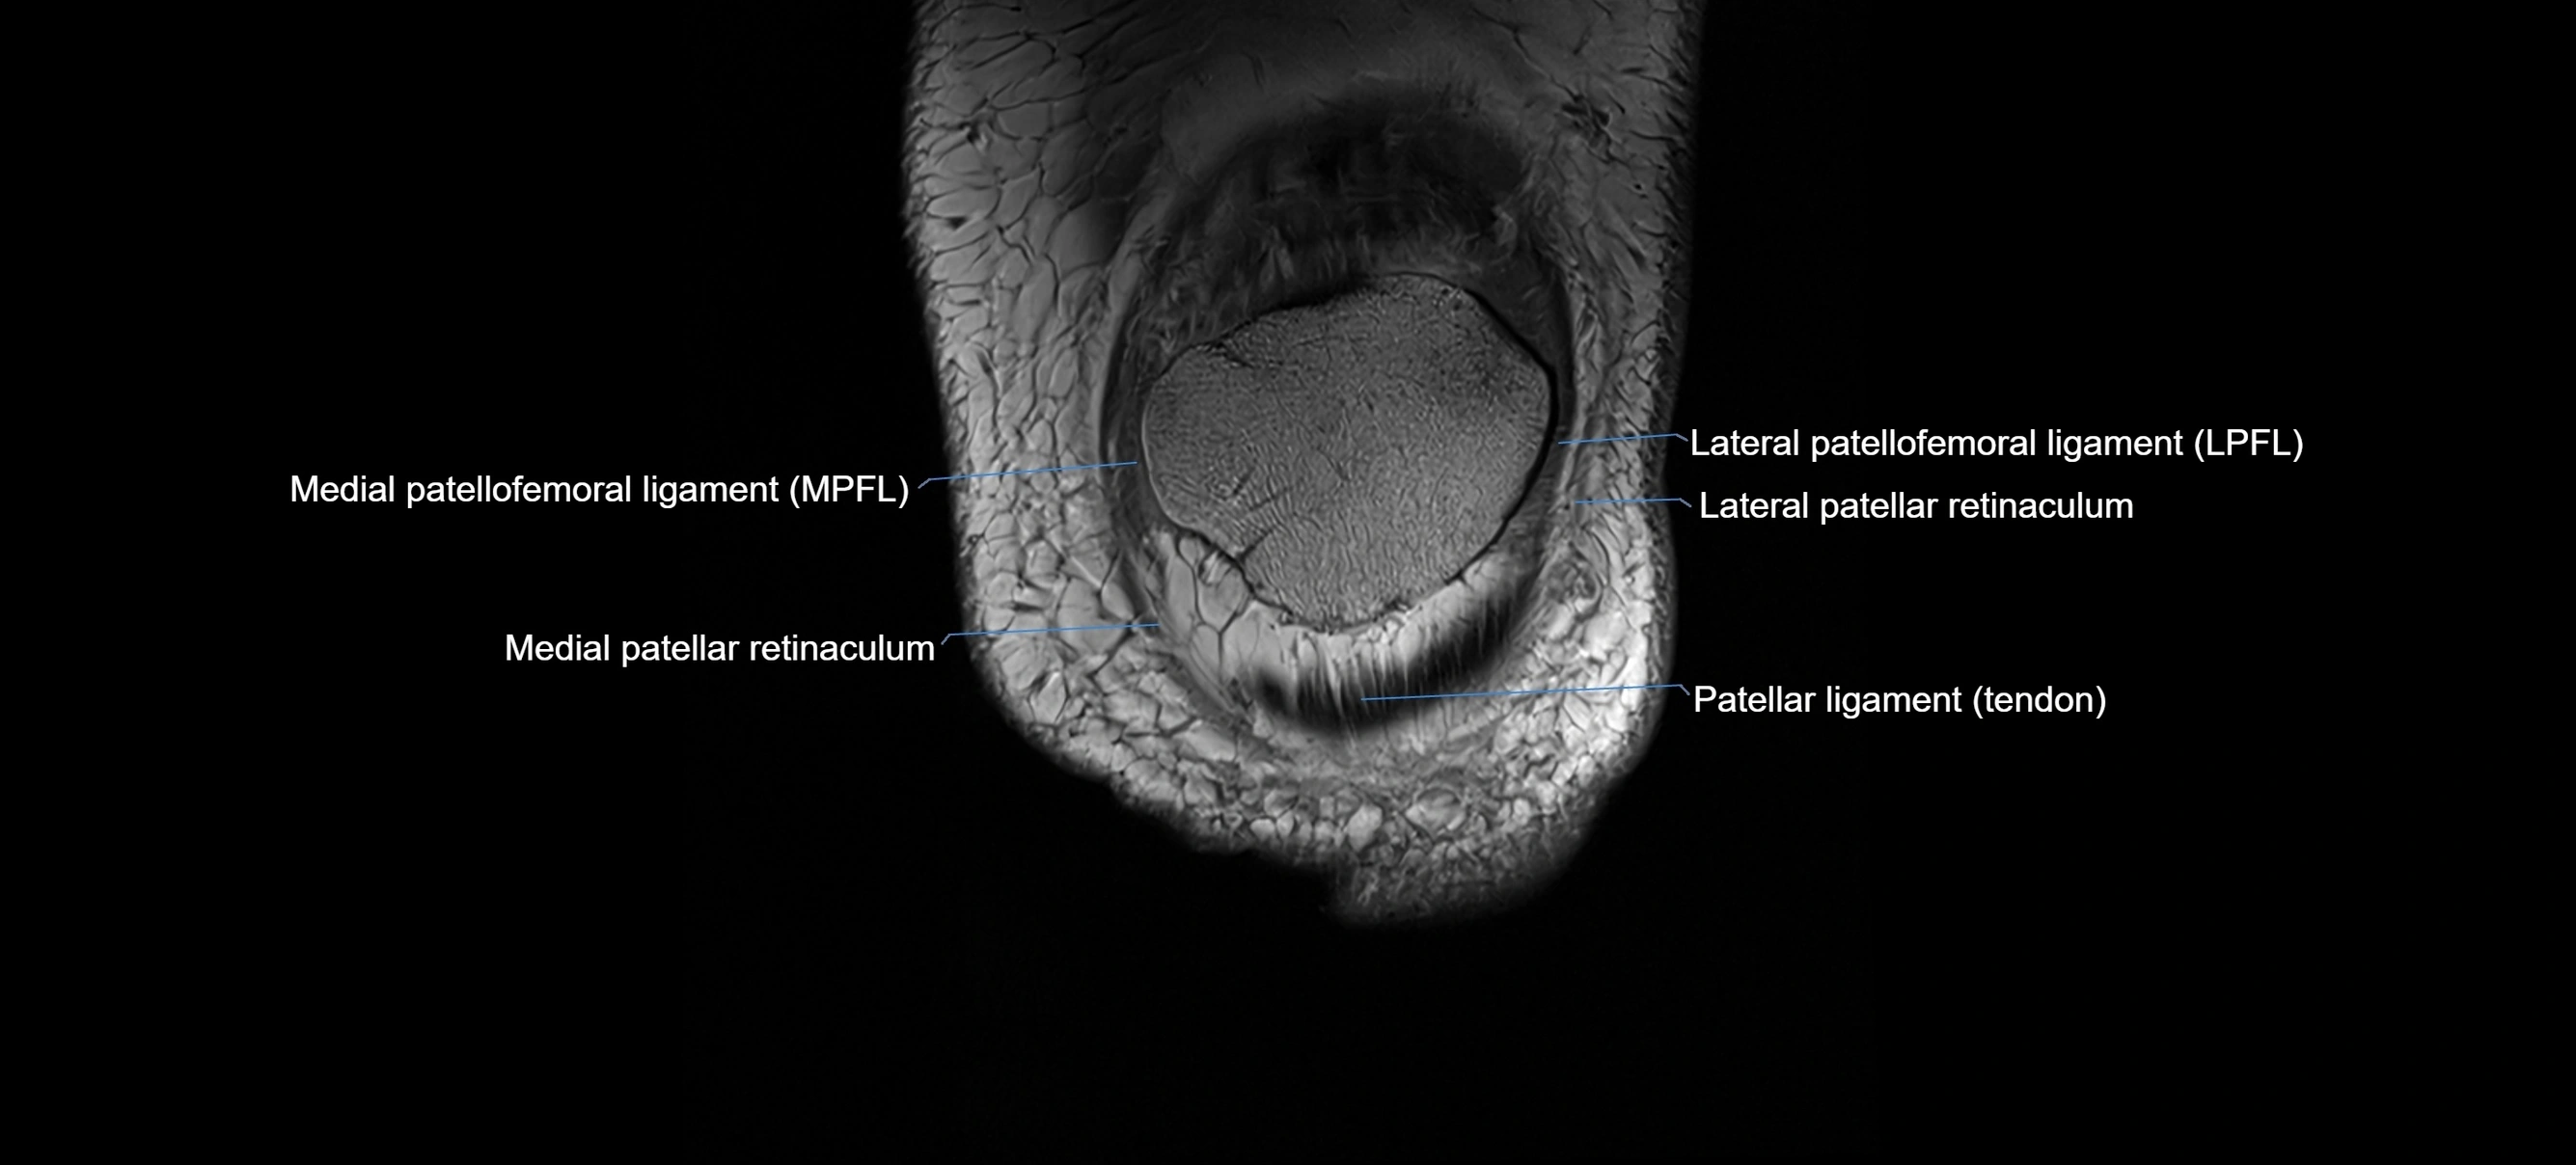

MRI images

image